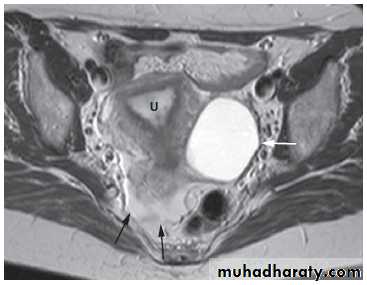

At CT fibroids are usually the same density as the adjacent myometrium. MRI can readily identify fibroids as they typically have a different signal characteristic from the normal uterus .

Adenomyosis

Adenomyosis is a benign condition in which there is endometrial tissue within the myometrium. This results in smooth muscle hypertrophy. Patients may present with dysmenorrhoea and abnormal uterine bleeding. The uterus is typically enlarged.On ultrasound, there is increased heterogeneity of the myometrium.

On MRI, there is focal or diffuse thickening of the junctional zone and, in some cases, multiple bright projections are seen extending from the endometrium into the myometrium .